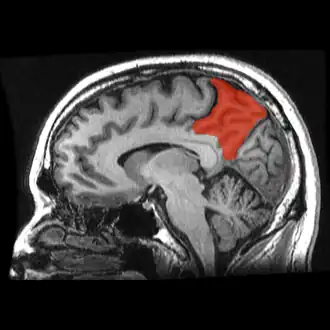

![]() Corte de una IRM sagital mostrando el precúneo en rojo. | ||

Se denomina precuña o precúneo a una parte del lóbulo parietal superior oculto en la fisura longitudinal medial entre los dos hemisferios cerebrales. A veces se describe como la zona media de la corteza parietal superior. El precúneo está limitado anteriormente por la rama marginal del surco cingulado, posteriormente por el surco parietooccipital, e inferiormente por el surco subparietal. Está involucrado con la memoria episódica, procesamiento visuoespacial, reflexiones sobre uno mismo, y aspectos de la conciencia.

Anatomía

El precúneo es una pequeña circunvolución en forma de cuña en la superficie medial del lóbulo parietal del cerebro, delimitada posteriormente por el surco parietooccipital y anteriormente por el lóbulo paracentral.